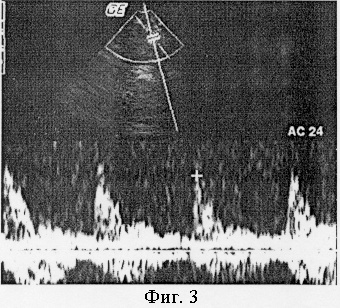

Пример 2. Пациент Н. 52 лет, с клиническим диагнозом «ишемическая миелопатия», диагноз верифицирован при МР-томографии. Спектр кровотока в артерии Адамкевича представлен на фиг.3. Кровоток имеет значительно более низкоскоростной и низкорезистивный характер, пиковая систолическая скорость 0,29 м/сек, индекс периферического сопротивления RI=0,60.